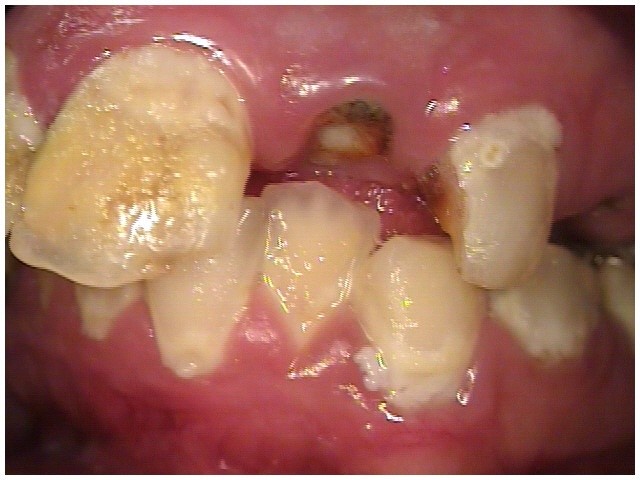

The patient in Figure 10 through Figure 12 was pregnant when she presented for dental treatment. The pregnancy was unplanned and she had had a lack of prenatal care. Continuing meth use during the pregnancy resulted in a positive toxic baby. She stated that she had just stopped using meth and had entered a rehabilitation facility a few days before. She was brought to the author’s clinic with a toothache. Note that as seen in these images, extreme accumulation of plaque, lack of oral hygiene, and severely decayed and missing teeth are classic manifestations in meth users.

Fig 10. Accumulation of soft plaque is typical of oral hygiene neglect associated with the use of methamphetamine.

Figure 10

Fig 11. Note demineralization of smooth surfaces, carious lesions at the gingival margins, and associated inflammation of the periodontium.

Figure 11